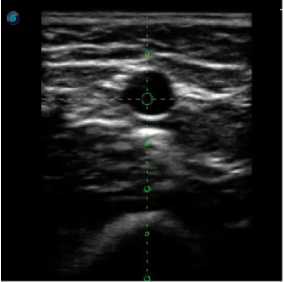

實(shí)時(shí)觀察穿刺針進(jìn)入血管的全過(guò)程,方便操作及較短的穿刺路徑,智能進(jìn)針尺寸提示,讓置管工作更加輕松,高效。

不同進(jìn)針路徑